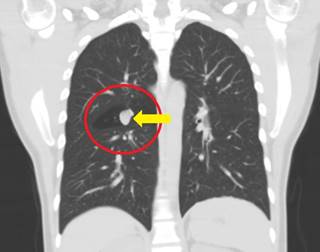

En consulta de neumología presentó radiografía de tórax en la que se observó una lesión focal «en dedo de guante» en la región parahiliar derecha y alteraciones intersticiales mixtas apicales (Figura 2). Se amplió estudio de dichos hallazgos con TAC de tórax y se observaron alteraciones intersticiales nodulares y tractos fibrosos apicales bilaterales, con lesión ovalada en segmento superior de lóbulo inferior derecho (LID) con densidad cálcica en su interior, de aspecto benigno y, adicionalmente, atenuación en mosaico generalizada (Figuras 3-5). Durante la consulta no mencionó historia de tuberculosis pulmonar o contacto con sintomáticos respiratorios. Tenía exposición a vapores de soldadura y material particulado durante su vida laboral. Algunos síntomas gripales ocasionales.

Figura 3: Tomografía de tórax. Las flechas muestran alteraciones intersticiales nodulares y tractos fibrosos apicales bilaterales.

Figura 5: Tomografía de tórax. El círculo rojo enmarca una lesión ovalada en segmento superior de lóbulo inferior derecho con densidad cálcica en su interior, de aspecto benigno.